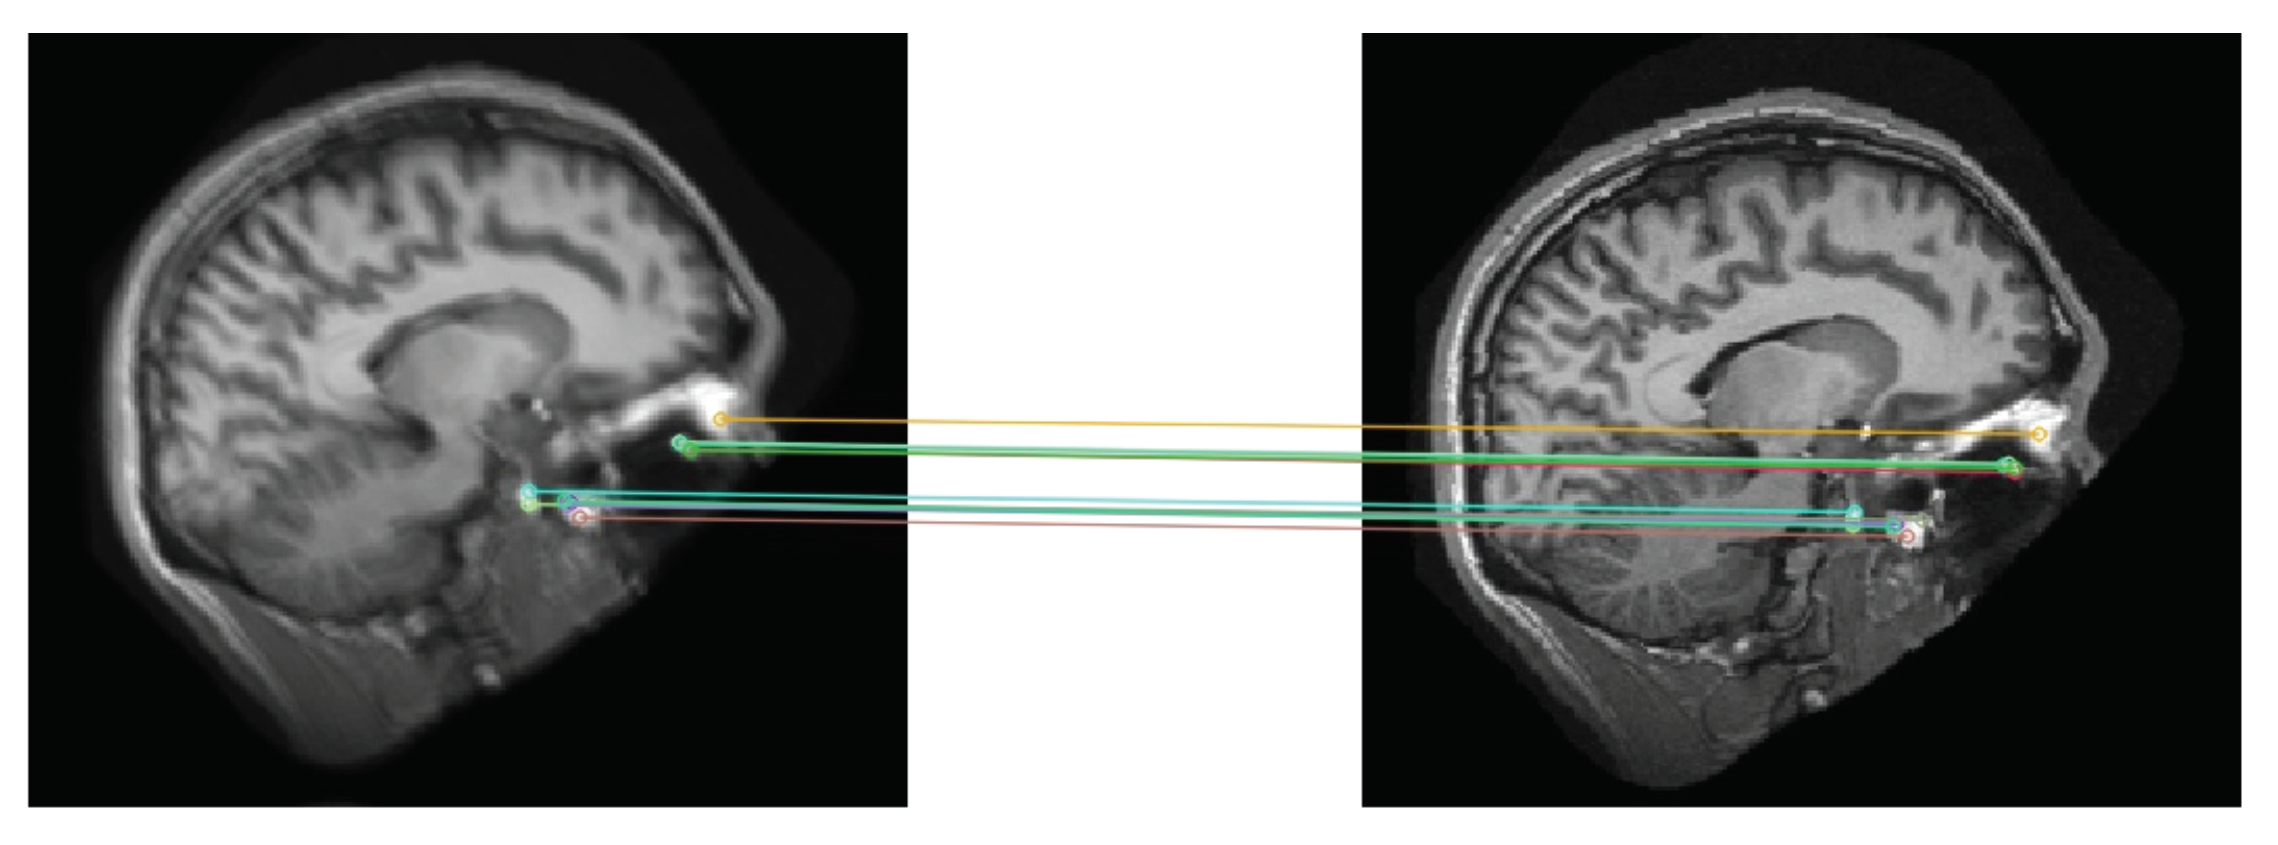

4. Data and Preprocessing

4.1. Real-World Datasets